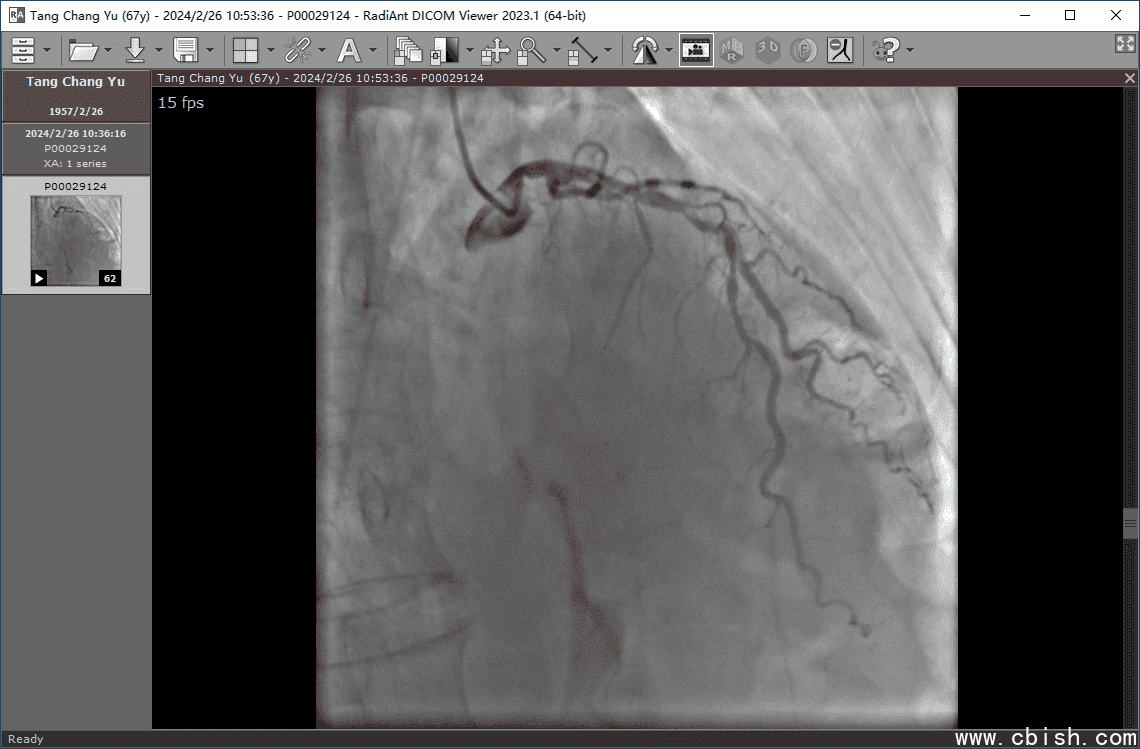

作为专为心血管影像量身打造的高性能DICOM查看与播放工具,RadiAnt DICOM Viewer 2025.1 在心脏造影(冠状动脉造影)领域持续领跑。无论是临床诊断、术前评估还是术后随访,这款软件凭借其精准的帧率控制、流畅的动态回放能力与高保真图像渲染技术,成为放射科医生、心内科医师及介入手术团队不可或缺的影像分析助手。

与传统通用型DICOM查看器不同,RadiAnt 2025.1 深度优化了对动态序列(如旋转造影、心动周期序列)的支持,可无缝播放长达数分钟的冠状动脉造影视频流,支持最高60帧/秒的实时播放,确保微小血流变化和病变细节清晰呈现。

软件内置智能缩放、多平面重建(MPR)、曲面重建(CPR)及三维血管成像(3D-DSA)功能,配合精确的测量工具(如狭窄程度计算、长度/直径标定),帮助医生快速定位斑块位置、评估狭窄程度,提升诊断效率与准确性。